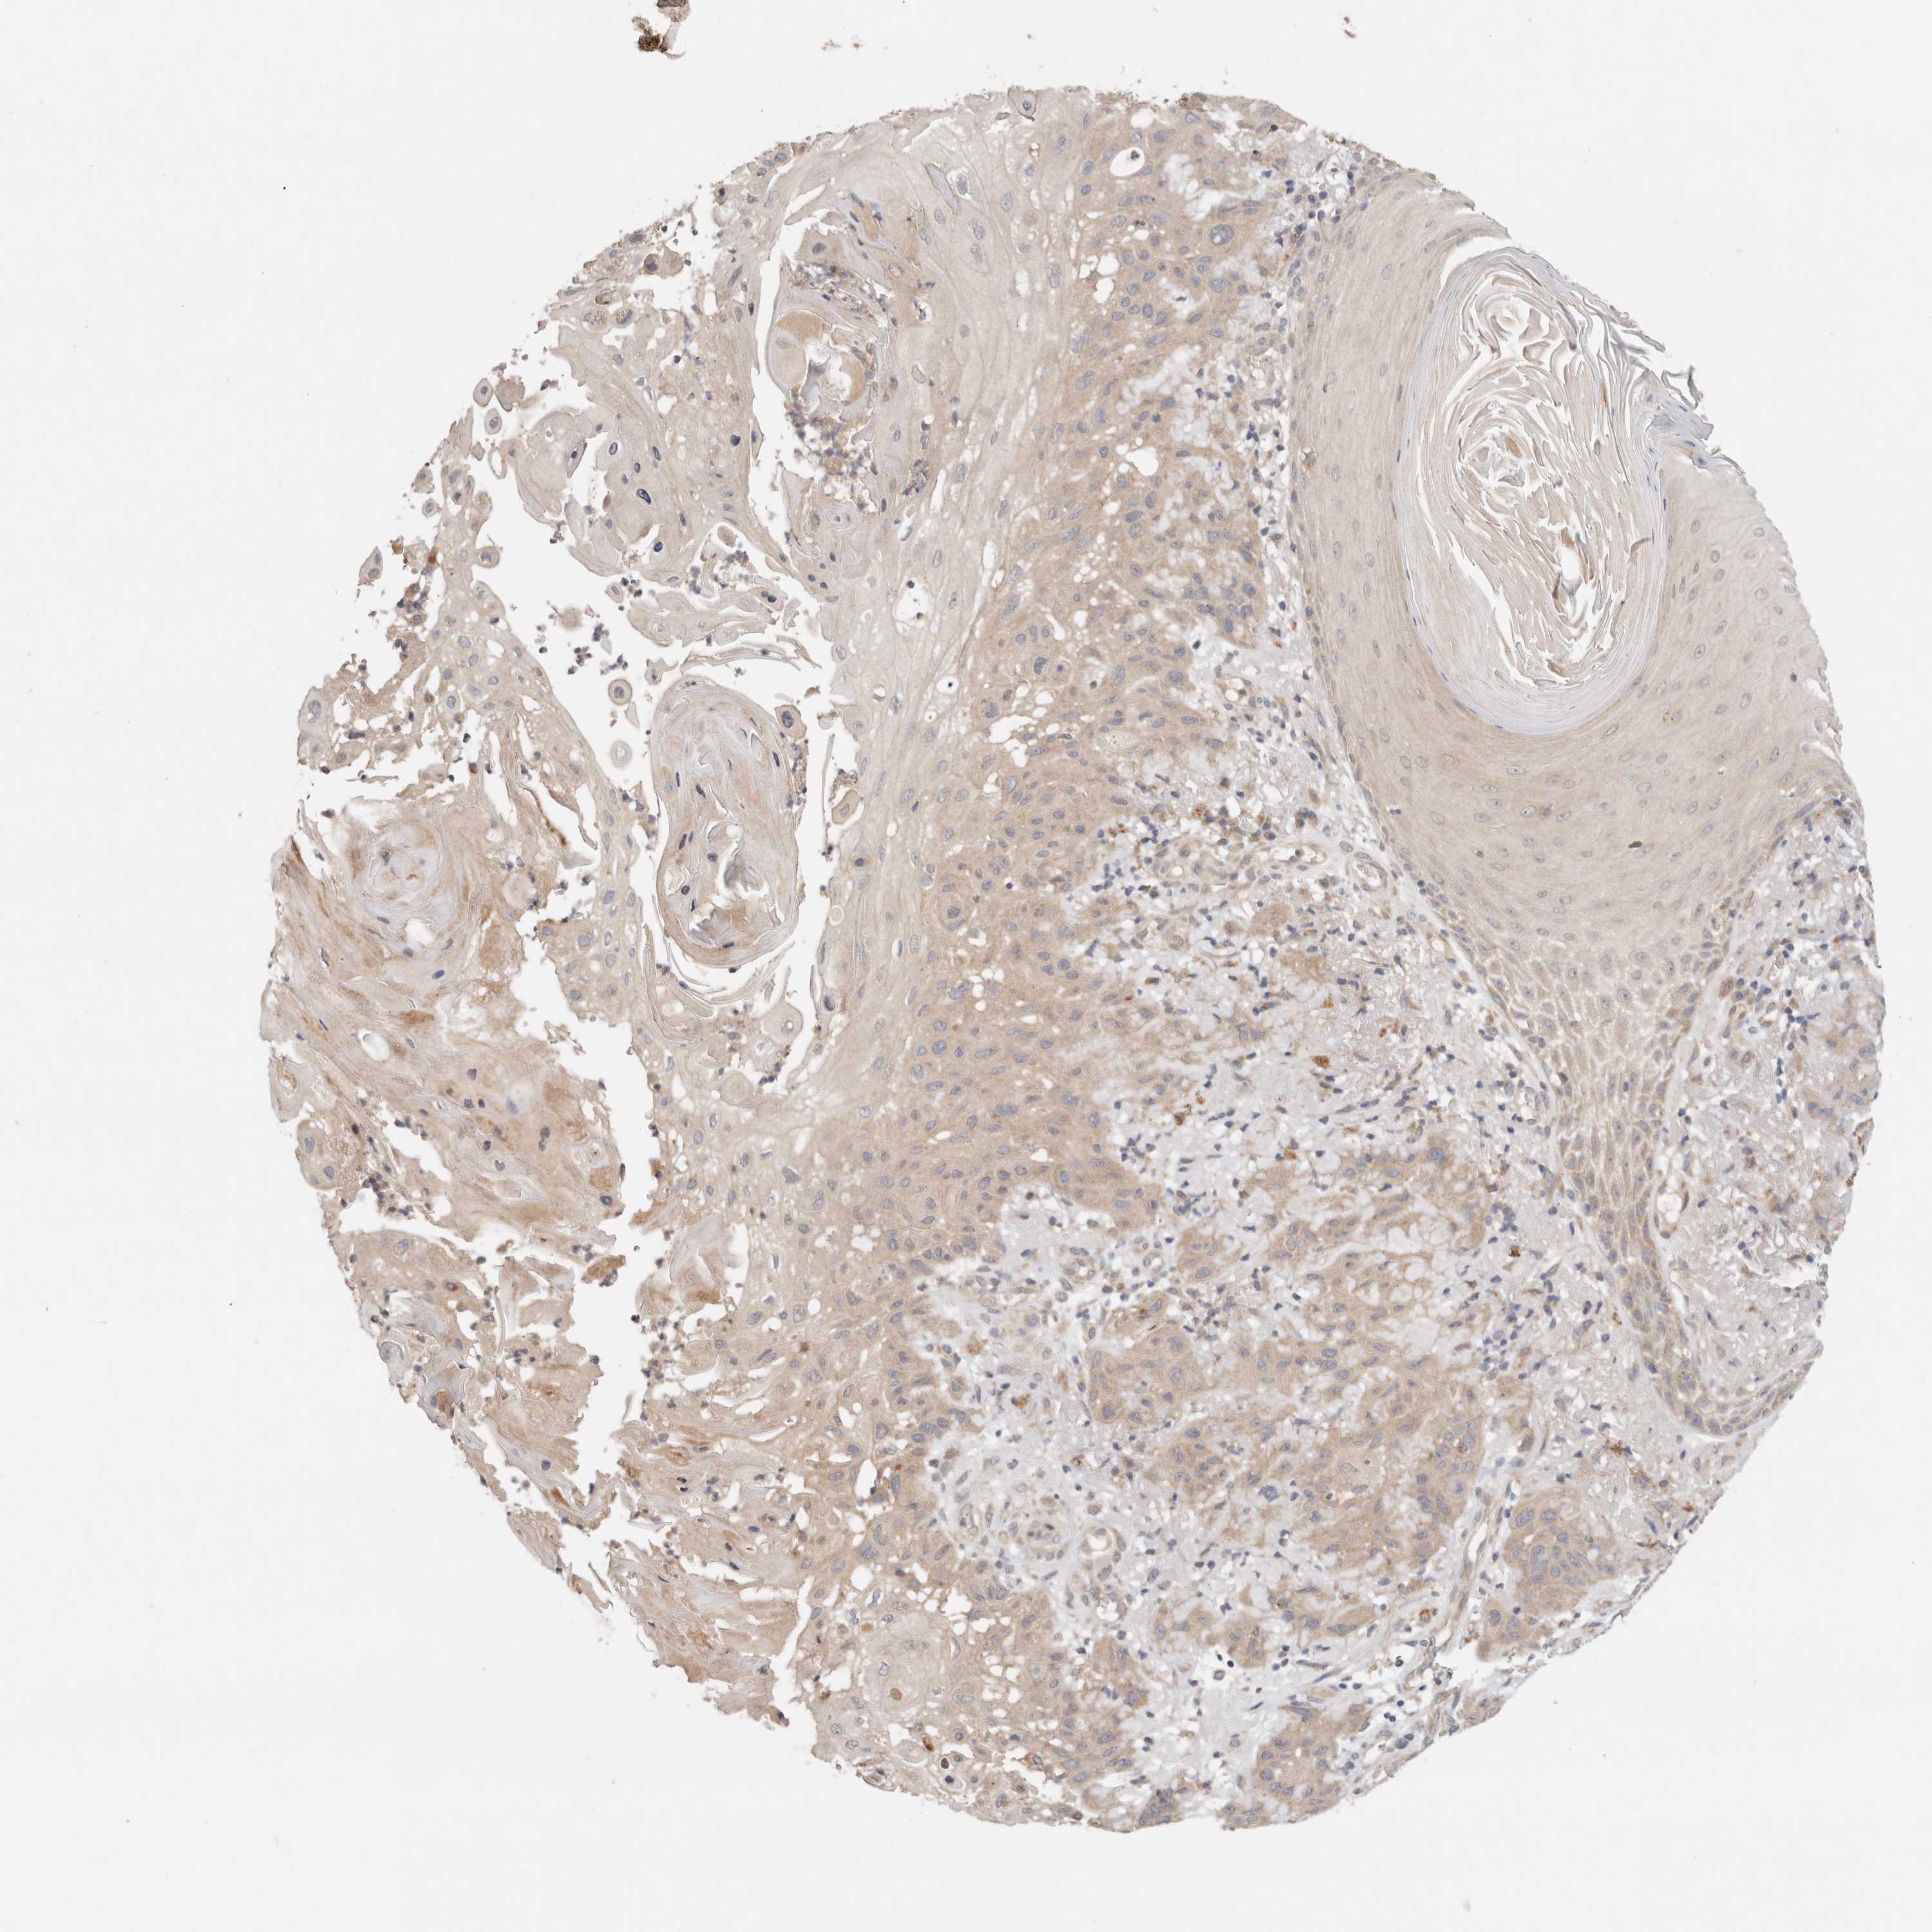

SKIN CANCER - Protein expressioni

A mouse-over function shows sample information and annotation data. Click on an image to view it in a full screen mode. Samples can be filtered based on level of antibody staining by selecting one or several of the following categories: high, medium, low and not detected. The assay and annotation is described here.

Each image is clickable and will lead to virtual microscopy that enables deeper exploration of all samples and also displays staining intensity scores, fraction scores and subcellular localization as well as patient and tissue information for each sample.

Antibody CAB025148

Staining

Medium

Basal cell carcinoma

Squamous cell carcinoma, NOS